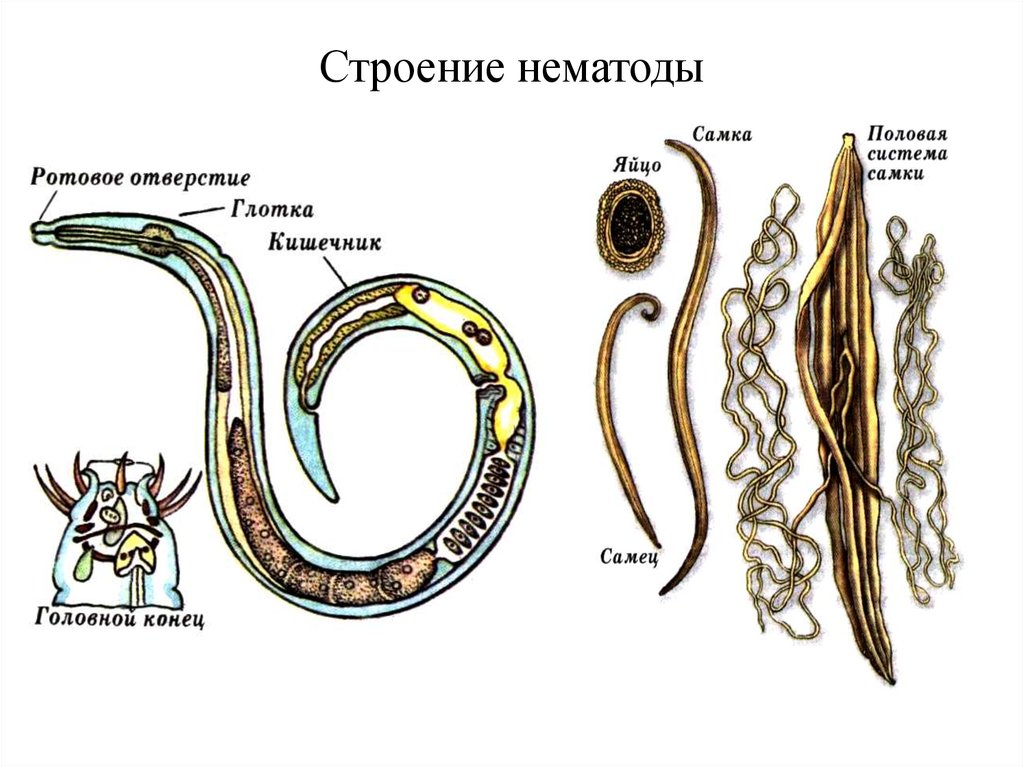

Фотографии нематод, цестод и трематод в природе